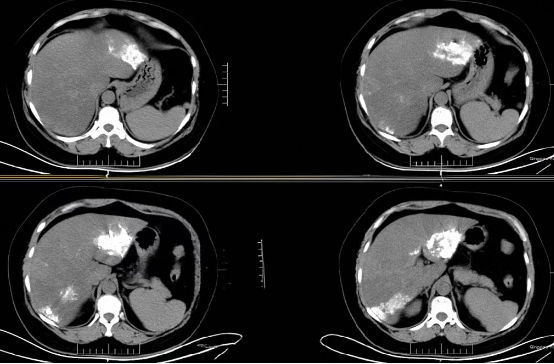

术前增强CT示肝内多发血管瘤

术后复查CT,瘤体内碘油沉积良好

术前增强CT示肝右叶肿块伴门脉瘤栓形成

术后复查CT,可见瘤体内碘油沉积良好